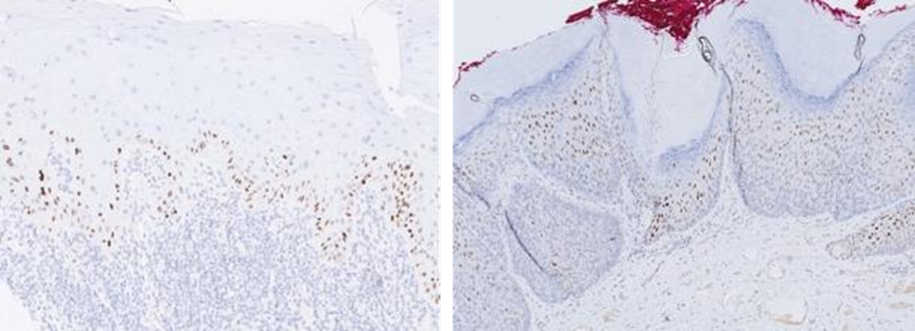

Tolkning av p16-färgning: I LAST-projektet fastställs att endast stark och utbredd "block"-p16-färgning bör betraktas som "positiv". I skivepitel definieras detta som en sammanhängande stark kärn- plus cytoplasmatisk färgning av basalcellsskiktet med förlängning uppåt som vanligen inbegriper minst en tredjedel av den epiteliala tjockleken. Denna höjdbegränsning är något godtycklig och framför allt i keratiniserande skivepitel kan positiviteten vara begränsad till de basala delarna (Fig. 3). Observera alltså att ett prov kan kallas positivt utan färgning av hela epitelets tjocklek. Alla övriga mönster tolkas som negativa, inklusive fläckvis mosaikfärgning. Fokal eller ojämn kärnfärgning är ospecifik och kan ses vid reaktiv skivepitelmetaplasi, liksom vid låggradig lesion (LSIL). För fler bildexempel på p16-färgning hänvisas till KVAST-dokumentet för cervixcancer.

Figur 3. Positiv p16-färgning i skivepitel kan i vulva vara relativt begränsad till de basala delarna av epitelet.